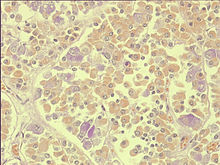

Zelltypen

Lichtmikroskopisch lassen sich durch unterschiedliches Färbeverhalten in der Adenohyphophyse drei Zelltypen unterscheiden. Es handelt sich dabei um azidophile, basophile und chromophobe Zellen.

Azidophile Zellen

Diese mit saurem Farbstoff anfärbbaren Zellen (azidophile Zellen) sind am häufigsten in der Adenohyphophse. Charakteristisch sind insbesondere rot anfärbbare Granula im Cytoplasma. Sie bilden ausschließlich nichtglandotrope Hormone und lassen sich in zwei Untergruppen einteilen:

Basophile Zellen

Dieser Zelltyp ist aufgrund der im Cytoplasma eingeschlossenen Sekretionsgranula mit basophilen Farbstoffen dunkelviolett-blau anfärbbar. Auch hier lassen sich je nach Hormonproduktion unterschiedliche Zelltypen unterscheiden, wobei alle außer den MSH-bildenden Zellen glandotrope Hormone bilden:

Chromophobe Zellen

Chromophobe Zellen sind nicht anfärbbar, da sie keine Granula besitzen. Zu den Chromophoben Zellen zählen Stammzellen, Sternzellen, die den Gliazellen im Nervensystem ähnlich sind, und verbrauchte endokrine, vormals azido- oder basophile Zellen, die keine Granula mehr besitzen.